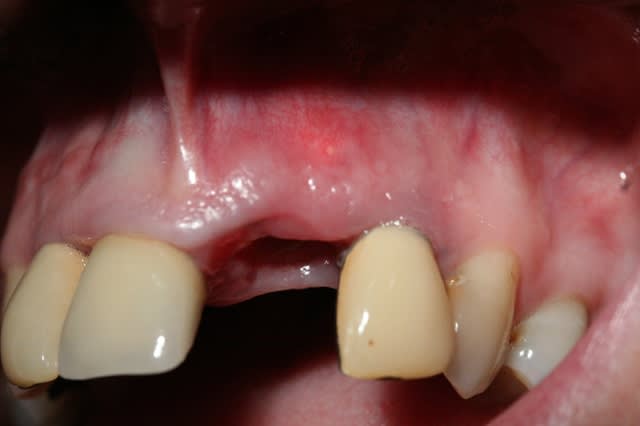

il y a selon moi perte de la table externe que j'estime à 2 mm de large et 3 à4 mm de haut.

je viens de revoir la patiente ce matin.

je commence à obtenir une gencive vestibulaire , ce qui me permettra de gérer la gencive plus facilement. je n'aurais donc peut être pas besoin de mettre la rustine que tu conseilles.

oui, mais c'était parfaitement prévisible, je n'ai pas fermé l'avéole. peut être inutile à ce stade.

j'espère seulement garder un peu de volume là où il en reste.